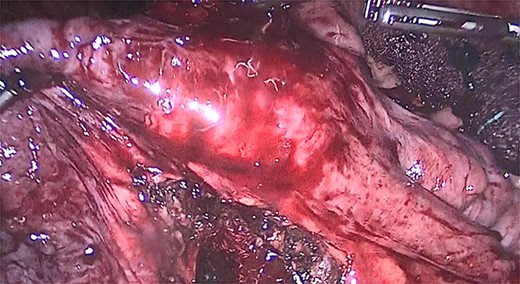

We performed adhesiolysis, used a harmonic scalpel to release intestinal loops and identified the gastric pouch (which was tight and measured < 15 cm long), remaining stomach, gastrojejunostomy and the common limb (∼200 cm), the total intestinal length was 600 cm (Fig. 2). We proceeded to make a new gastric pouch with a black staple (60 mm) and performed a gastro-gastro anastomosis with a purple staple (45 mm) (Fig. 3). The angle of Treitz was identified, and we found the jejunojejunostomy at 200 cm (Fig. 4). We later identified the gastroileal anastomosis, proceeded to resect that segment of 15 cm (Fig. 5) and the surgical procedure was completed.